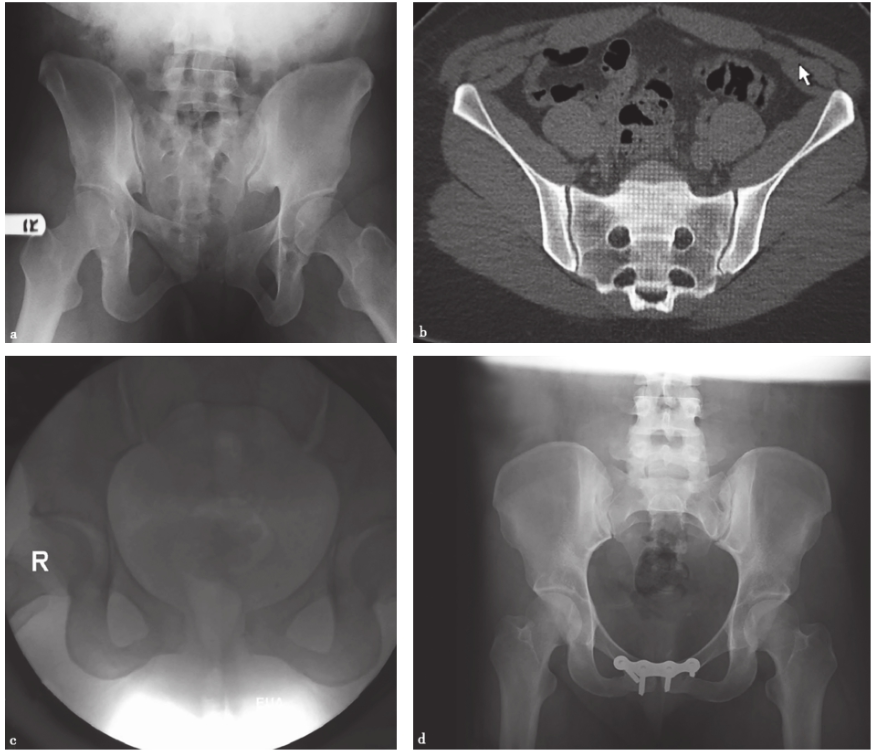

在常规的X线检查中,一些细微的失稳是无法观察到的,只有通过特殊的检查方法才能识别。Sagi等术前在麻醉下对68例骨盆后环的不完全损伤(OTA61-B型)进行X线和CT检查。他们认为在麻醉下进行的动态应力透视检查显示,50%的前后挤压型(anteroposteriorcompression,APC)Ⅰ型损伤、39%的APCⅡ型损伤和37%的侧方挤压型(lateralcompression,LC)Ⅰ型损伤都有隐性失稳(图11)。

图11骨盆后环的不完全损伤影像a.骨盆正位X线片示APCⅠ型损伤;扫描显示无明显骶髂前韧带损伤;c.外部旋转应力下透视显示为耻骨联合分离2.5cm的旋转不稳定型,即APCⅡ型损伤;d.对隐匿性APCⅡ型损伤的内固定术后

使用CT检查可以充分显示骨盆后方与韧带的结构。尤其是当骶骨骨折伴有大量肠气和粪便时,骨盆X线片容易造成漏诊,这时CT检查就非常有帮助。CT三维及多平面重建可获得任意平面的图像及任意旋转的三维立体图像,为临床医师整体、全面观察骨盆骨折提供了直观立体的图像,为骨折类型的诊断及手术设计提供了极大的帮助。骨盆受到外力损伤后骨性三维成像可清晰、完整地显示整个骨盆损伤后的形态变化及骨折情况,特别是对有移位的断端,在三维重建模式下可全面地了解断端上下、左右、前后的移位及程度,对于X线片不能发现疑似的隐匿性骨折,也可以在多平面重建成像中得以证实或排除。因此,三维成像的结果对实施手术的方式和骨折的固定有很重要的指导作用,并可依此对患者进行预后评估。对于确定骨盆背侧损伤的机制,CT检查时可以发现通过骶骨的损伤是压缩伤还是剪切力损伤。骶髂关节移位程度对于确定背侧损伤的稳定性是很有价值的。若关节张开的程度继续加大,后方韧带将断裂,损伤将变为不稳定型(C型)。CT还有助于了解有无髋臼骨折。很多接近前柱的耻骨支骨折容易合并髋臼骨折,近年来发展起来的三维CT对骨盆骨折的诊断帮助更大。Obaid报道了174例骨盆骨折病例,其中51%被X线片漏诊,最后由CT确诊,这些骨折大多发生在骶髂区域(图13)。

图13骨盆骨折CT表现显示双侧骶骨骨折;三维重建显示右骶髂关节间隙增宽,耻骨联合分离,右髋臼横行骨折